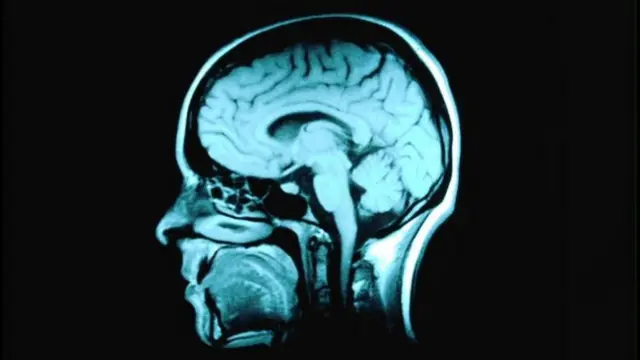

ที่มาของภาพ, Science Photo Library

นักวิทยาศาสตร์จากสถาบัน มักซ์ พลังก์ เพื่อการศึกษาด้านพันธุกรรมและชีววิทยาของเซลล์ระดับโมเลกุล ในเมืองเดรสเดนของเยอรมนี เผยแพร่ผลการศึกษาที่พบว่า การที่สมองของคนเรามีวิวัฒนาการโดยขยายขนาดจนใหญ่ขึ้นกว่าสัตว์ทั่วไปนั้น เกิดจากการกลายพันธุ์เฉพาะจุดในยีนตัวหนึ่งเมื่อหลายล้านปีก่อน ซึ่งส่งผลให้มีการสร้างเซลล์สมองเพิ่มมากขึ้นและสมองส่วนสำคัญที่เรียกว่านีโอคอร์เท็กซ์ขยายตัวขึ้น

นักวิทยาศาสตร์พบว่ามีการกลายพันธุ์เฉพาะจุดเกิดขึ้นในยีน ARHGAP11B ซึ่งมีการค้นพบเมื่อปีที่แล้วว่า ยีนนี้เป็นตัวการทำให้สมองส่วนนีโอคอร์เท็กซ์ ซึ่งเป็นสมองส่วนที่เกิดขึ้นใหม่ในบรรดาสัตว์เลี้ยงลูกด้วยนม มีการขยายขนาดขึ้นในมนุษย์ โดยคาดว่ายีนดังกล่าวเกิดขึ้นเมื่อราว 5-6 ล้านปีก่อน และการกลายพันธุ์เฉพาะจุดในยีนนี้ทำให้ภายหลังสมองส่วนนีโอคอร์เท็กซ์ของมนุษย์ขยายขนาด จนสามารถจุข้อมูลได้มากขึ้นและพัฒนาความสามารถขั้นสูงในการประมวลผลประสาทสัมผัส การใช้เหตุผลและความคิดเชิงนามธรรมที่ซับซ้อน รวมทั้งการใช้ภาษาด้วย